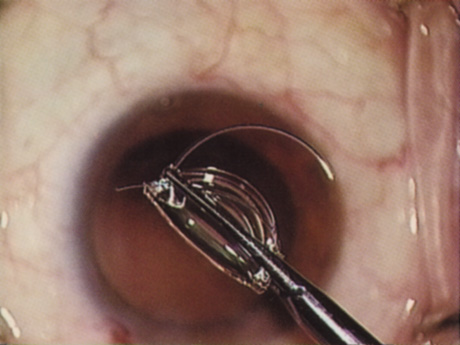

Phacoemulsification machines use either flow- or vacuum-based systems. Flow-based systems induce aspiration by directly creating flow within the tubing, whereas vacuum-based systems induce aspiration by first creating a vacuum. Most flow-based systems use peristaltic pumps (Fig. 13). Such pumps employ a series of rollers to pinch compliant tubing serially, thereby creating flow within the aspiration tubing. The vacuum level at the phacoemulsification tip rises when flow toward the pump meets resistance because of partial or full occlusion at the phacoemulsification tip. Computerized pump controls allow the surgeon to set vacuum limits and control flow rates. The surgeon can adjust these independently to balance the degree of hold-ability against the chance of chamber collapse.

Fig. 13. The Infiniti peristaltic pump (Alconlabs, Fort Worth, TX).

Aspiration tubing within a peristaltic pump must be compliant; high vacuum levels can induce an unexpected surge of flow as the compliant tubing springs open after a nuclear chip, occluding the tip is emulsified and aspirated (occlusion break). This phenomenon, known as postocclusion surge, can lead to sudden chamber collapse and thereby result in a posterior capsule rupture, or iris trauma. Some systems have sensors within the tubing to minimize a postocclusion surge by automatically shutting down the pump. Additionally, some systems offer minimally compliant tubing, minimizing postocclusion surge (Fig. 14). Aspiration bypass tips have a small hole within the side of the phacoemulsification needle, allowing continuous low flow, despite tip occlusion, and thereby reducing surge (Fig. 15).

Fig. 14. MaxVax tubing (Alcon Laboratories, Ft. Worth, TX) has thicker walls that limit compression and, thereby, postocclusion surge.

Fig. 15. The aspiration bypass tip (ABS) (Alcon Laboratories, Fort Worth, TX).